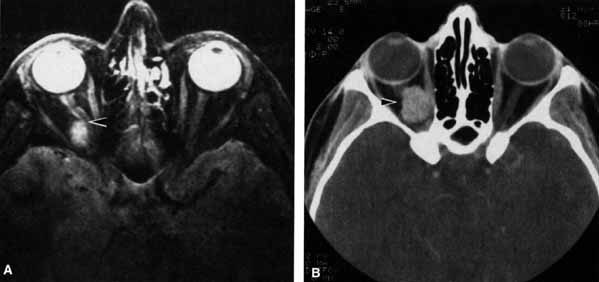

CASE 1 A 70-year-old woman presented with a 6-month history of progressive diplopia and ptosis. She demonstrated complete right third, fourth, and sixth cranial nerve palsies, and hypesthesia of cranial nerve V1 (Fig. 22A). The right pupil was dilated. Computed tomography (CT) disclosed an intracavernous aneurysm (see Fig. 22B). The so-called superior orbital fissure syndrome occurs when an infiltrative, inflammatory, or ischemic event occurs within the superior orbital fissure, but not in the orbital apex.4 A complete superior orbital fissure syndrome occurs when all the neurovascular components passing through the superior orbital fissure are damaged, producing a total ophthalmoplegia, ptosis, and anesthesia of cranial nerve V1 (see Fig. 22A). The pupil may be dilated, miotic, or midposition and fixed, depending on the balance of parasympathetic and sympathetic damage. The superior ophthalmic vein, best seen on CT, may be dilated if venous outflow from the orbit is obstructed. Clues to venous outflow obstruction are increased intraocular pressure, fullness of the upper eyelid, and hyperemia of the deep Tenon's vessels. Ophthalmoscopically, the retinal veins may be dilated. The effect of a lesion in the superior orbital fissure or the anterior cavernous sinus cannot be differentiated clinically (see Fig. 22B). When the posterior cavernous sinus becomes involved, hypesthesia of cranial nerve V2 may also be present. The only difference between a superior orbital fissure syndrome and an orbital apex syndrome is the presence of visual loss caused by optic nerve involvement. Visual acuity, color vision, or the visual field are abnormal. An ipsilateral relative afferent pupil defect is present. CASE 2 A 30-year-old man noted diplopia and right ptosis for the past month. The patient demonstrated normal vision and symmetric pupils but had a neurogenic ptosis (Fig. 23A) and limited right supraduction (Fig. 23B). Otherwise his extraocular movements were full. CT demonstrated an intracranial aneurysm of the posterior communicating artery aneurysm (Fig. 23C). Anatomically, the third cranial nerve branches into its superior and inferior divisions as it enters the orbit through the superior orbital fissure. Superior branch damage results in ptosis (levator muscle) and decreased supraduction (superior rectus muscle). Inferior branch damage results in decreased adduction (medial rectus), decreased infraduction (inferior rectus), decreased excycloduction (inferior oblique), and a dilated pupil (parasympathetic). Anatomically, a cranial nerve III branch nerve lesion seems to imply an anterior cavernous sinus or orbital apex localization. However, functionally, the third cranial nerve may bifurcate in the intracranial portion of the nerve, so cranial nerve III branch nerve palsies have been demonstrated with intracranial lesions. The localizing finding of a cranial nerve III branch nerve lesion is therefore not absolute (see Fig. 23).46 CASE 3 A 12-year-old child was referred by his school nurse because he had been complaining intermittently of double vision and the nurse had noted intermittent right ptosis. The child presented with a right ptosis and limited infraduction of the left eye (Fig. 24A). The ptosis worsened with prolonged up-gaze. A Cogan lid twitch was noted on the right with upward saccades. Injection of 1 mg of edrophonium resulted in complete resolution of diplopia and ptosis (Fig. 24B). The diagnosis was myasthenia gravis. Most orbital and cavernous sinus lesions produce afferent and efferent palsies in an anatomic pattern, for example, the superior orbital fissure has cranial nerves III, IV, VI and V1. When the pareses are not localized anatomically, or when there is variability in findings over time, one should include carcinomatosis or myasthenia gravis (see Fig. 24) in the differential diagnosis. Fatigability and a Cogan lid twitch strongly suggest myasthenia gravis. CASE 4 A 52-year-old woman presented with diplopia when looking to her right. She had noted a red right eye for the past 3 months (Fig. 25A). Visual acuity was 20/20 in both eyes and the pupils were normal. The right eye was limited in abduction. Forced duction testing showed abduction of the right eye to be restricted. Intraocular pressures were 23 mm Hg OD, and 15 mm HG OS. CT showed a dilated right superior ophthalmic vein (Fig. 25B) which was shown to be caused by a dural cavernous fistula. The right medial rectus muscle was also enlarged (Fig. 25C) because of blood engorgement, reducing muscle compliance, which accounted for the restricted abduction. Carotid cavernous fistulas can develop either as a result of trauma or spontaneously.47 A direct carotid cavernous fistula results from a tear in the intracavernous carotid artery with arteriolization of the cavernous sinus and superior orbital vein. Concomitant cranial nerve III, IV, VI, V1 and V2 paresis, elevated intraocular pressure, proptosis, and distention of the deep Tenon's vessels anteriorly (see Fig. 25A) with neuroradiologic evidence of an enlarged superior ophthalmic vein are common (see Fig. 25B). Ophthalmoplegia may also occur on a restrictive basis because of engorgement of the extraocular muscles with blood (see Fig. 25C).36 Dural carotid cavernous fistulas occur where small branches of the intracavernous carotid rupture, allowing access of arterial blood to the cavernous sinus. Typically, the findings are similar to a direct carotid cavernous fistula but of less magnitude. There is no history of trauma, and typically occurs in older persons. However, there is crossover between these two types of carotid cavernous fistula. An excessive ocular pulse tonographically may be helpful in the diagnosis of a carotid cavernous fistula in such cases.48 CASE 5 A 51-year-old woman was referred by her internist for left proptosis. The patient had noted diplopia for the past month but denied blurred vision or pain. Past history was significant for breast carcinoma requiring mastectomy. Vision was 20/20 in both eyes and the pupils were normal. Extraocular movements of the right eye were limited. Forced ductions were restricted. Exophthalmometry readings were 14 mm OD and 18 mm OS (Fig. 26A). CT disclosed a mass encircling the right globe (Fig. 26B). Biopsy disclosed metastatic scirrhous breast carcinoma retracting the right globe.